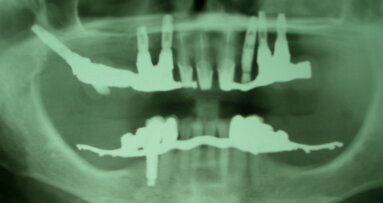

Riportiamo alcune considerazioni su un case report descritto da un odontologo forense con oltre trent’anni di esperienza, tacendo, per ovvi motivi di ...